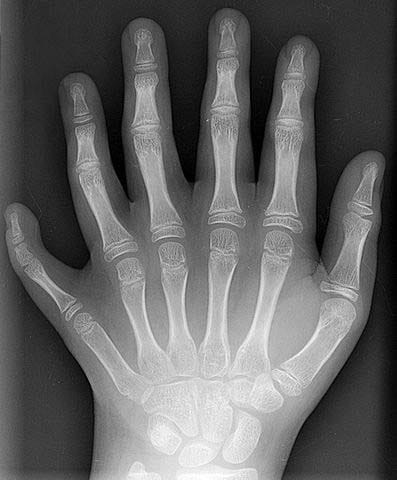

Fig 2 An example of polydactyly on x-ray. This patient had a duplication of their middle finger.

An example of polydactyly on x-ray. This patient had a duplication of their middle finger.